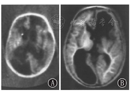

1 头颅MRI评估的发展历史早在1983年,Johnson等[3]首次报道了头颅MRI应用于新生儿脑发育及损伤的评估,展示了从胎龄36周至出生后20月龄不同时期髓鞘化的水平(图1);同时提供了早产儿脑室旁出血和后期白质软化、侧脑室扩张等病变(图2)。

早产儿脑室旁出血和后期白质软化、侧脑室扩张 A:纠正胎龄35周时;B:2岁时

Periventricular hemorrhage and late white matter softening and la-teral ventricular dilatation in premature infants A:at 35 weeks postmenstrual age;B:magnetic resonance imaging at 2 years old